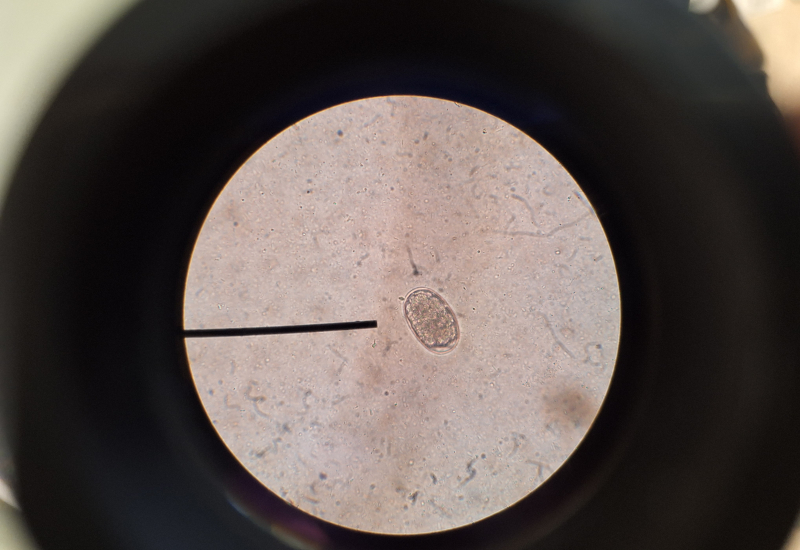

Wormen kunnen zich goed verstoppen, U hoeft niet altijd iets aan de buitenkant van uw dier te zien of in de ontlasting. Uw dier kan het hele jaar door besmet worden. Wormeieren komen binnen en buiten voor en een infectie bij uw huisdier kan zonder zichtbare klachten verlopen, waardoor het lijkt of uw huisdier geen worminfectie heeft. Een besmetting is echter zo opgedaan niet alleen bij uw huisdier, maar ook bij uzelf. Het is daarom belangrijk om uw huisdier ook uit voorzorg te ontwormen en te zorgen voor een goede hygiëne. Een juiste dosering en een juist en goed werkzaam ontwormingsmiddel.

Regelmatig ontwormen doorbreekt de levenscyclus van wormen en vermindert het risico dat worminfecties zich verspreiden van kat tot kat of van kat tot mens.